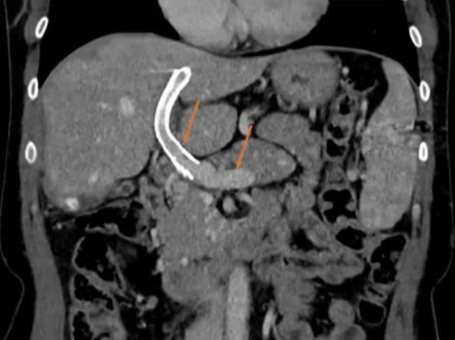

该程序包含以下步骤: 经脾脏入路:在超声引导下,刺穿脾静脉内的一个实质内分支。 在通过脾静脉造影确认了静脉通路后,导管和导丝被推进,以穿过脾静脉并抵达血栓化的门静脉。在门静脉/右门静脉分支处放置圈套器,为TIPS穿刺精准定位。TIPS穿刺圈套器,并穿过圈套器完成TIPS

步骤: 鉴于慢性血栓形成的复杂性: 一种经脾脏途径的门静脉再通术(PVR)。 随后是经颈静脉肝内门体分流术 。

结果:术后影像学检查显示门静脉和脾静脉的血流情况有所改善,且残留血栓极少。

通过经颈静脉肝内门体分流术(TIPS)治疗慢性门静脉血栓时所涉及的技术复杂性和决策难题,尤其是在标准方法因血栓程度过重而无法实施的情况下更是如此。 采用脾经脏穿刺术治疗门静脉高压症的方法证明能够有效克服这些难题,从而成功实施了经颈静脉肝内门体分流术(TIPS)。 PVR-TIPS 作为一线治疗方案:PVR-TIPS 为慢性门静脉血栓的治疗提供了一种技术上可行的解决方案,克服了标准 TIPS 安装所面临的难题。 持久效果:该干预措施不仅恢复了门静脉的血流,而且在后续随访中还显示出持续的通畅性以及血栓的完全消散。